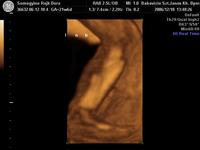

Itt egy pár kép az én pici fiamról.16-hetes rajta.És egyáltalán nem szégyenlös ami a képekböl is kitünik

Itt egy pár kép az én pici fiamról.16-hetes rajta.És egyáltalán nem szégyenlös ami a képekböl is kitünik